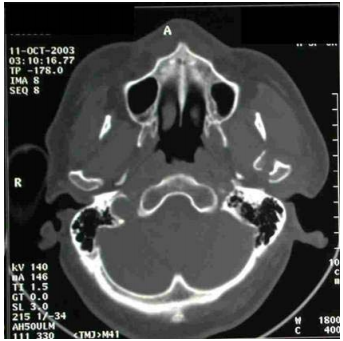

10.下圖是頭部電腦斷層影像,其診斷應是:

(A)右側上顎骨骨折 (B)右側下顎骨髁突(condylar process)骨折 (C)左側上顎骨骨折 (D)左側下顎骨髁突骨折